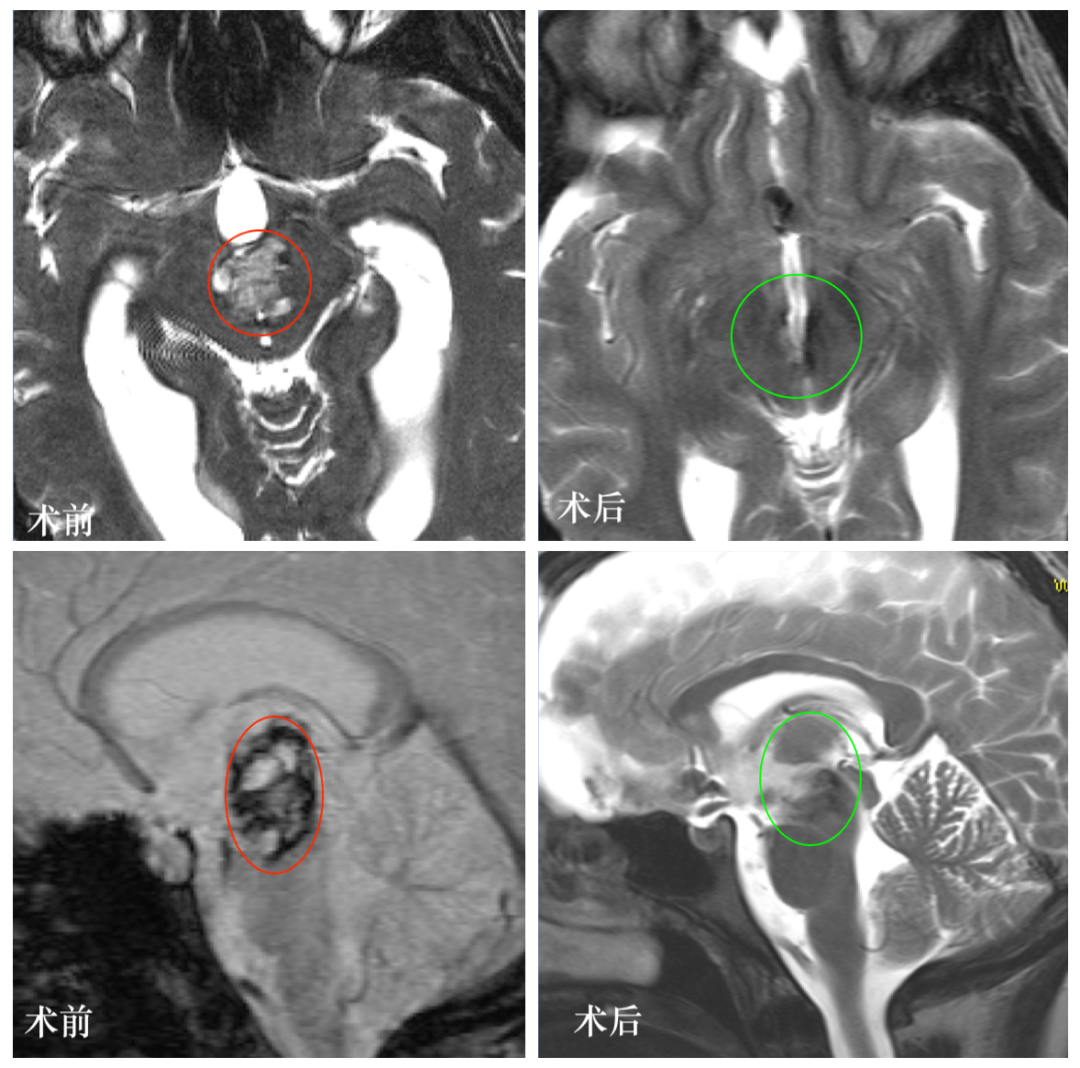

图:L同学颅脑MR显示中脑较大占位,混杂信号,海绵状血管瘤可能。

·术后2年:患者已经完成学业,取得本科学位,工作、生活正常如意,复查颅脑MR显示病变全切、没有复发,无任何神经功能损伤。图:手术前后颅脑MR对比,术后MR中脑脑干病变全切,无脑组织损伤等。